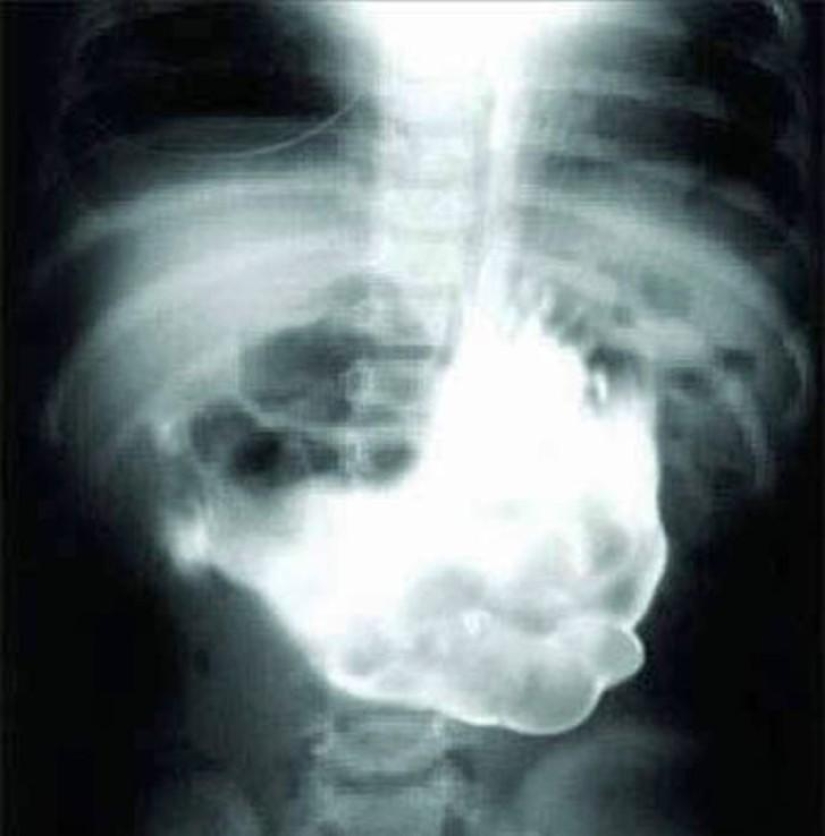

17. Una enorme bola de lana.